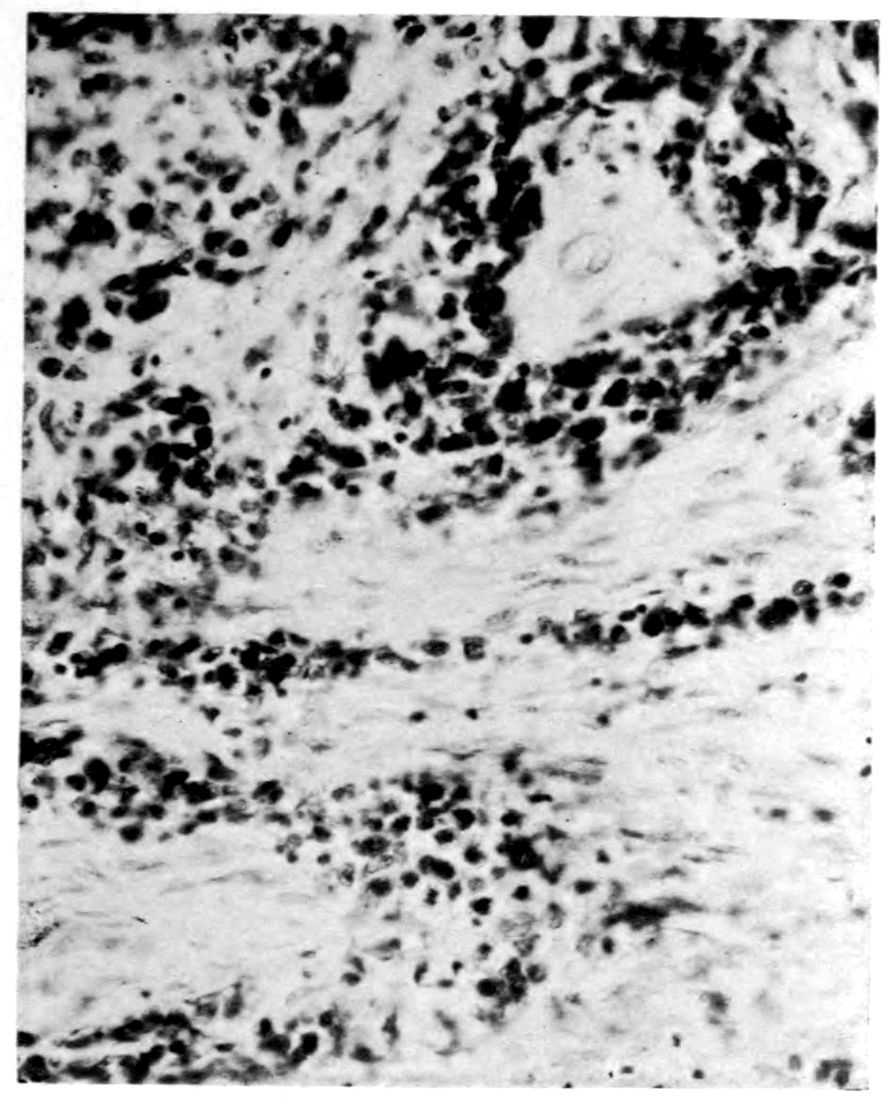

A. Normal postcentral cortex. (Compare B.)

B. Nerve cell losses. Perivascular deposits of mononuclear cells, amongst which are numerous plasma cells. Note decrease in number of nerve cells. Note irregular disposition of nerve cells. From paretic neurosyphilis.

Apparent new formation of small blood vessel. Photographed by Dr. A. M. Barrett.

Rod cells (Stäbchenzellen) in paretic neurosyphilis. Photographed by Dr. A. M. Barrett.

Granular ependymitis—microscopic appearance of a marked example of “sanding” of ventricle.